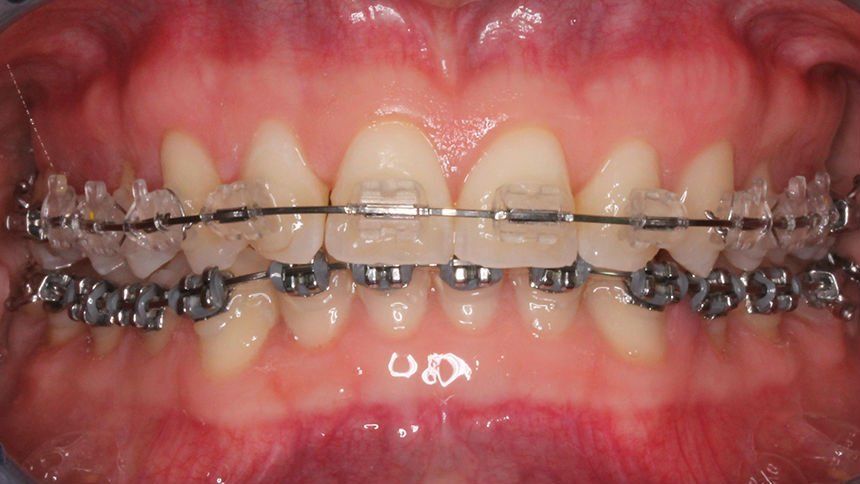

L'ortodonzia dell'adulto è solo ortodontica pura con solo spostamento dei denti, con sistema multi braket estetico trasparente oppure ortodonzia linguale, oppure con mascherine trasparenti (invisalign)

Ci sono vari metodi ortodontici per riuscire a raggiungere un bel sorriso, dall'ortodonzia multi-brackets metallica o trasparente

alla tecnica linguale agli allineatori trasparenti, quest'ultimi nell'ultimo periodo vengono molto richiesti.